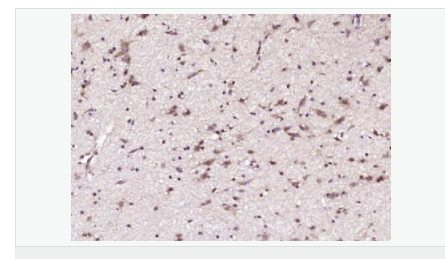

| 產(chǎn)品應(yīng)用 | WB=1:500-2000 ELISA=1:5000-10000 IHC-P=1:100-500 IHC-F=1:100-500 IF=1:50-200 (石蠟切片需做抗原修復(fù)) not yet tested in other applications. optimal dilutions/concentrations should be determined by the end user. |